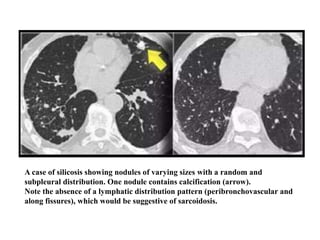

HRCT findings in Silicosis/CWP

• Small well-defined nodules of 2 to 5mm in diameter

in both lungs.

• Upper lobe predominance

• Nodules may be calcified

• Centrilobular and subpleural distribution

• Sometimes random distribution

• Irregular conglomerate masses, known as progressive

massive fibrosis

• Masses may cavitate due to ischemic necrosis.

• Often hilar and mediastinal lymphnodes.

A case of silicosis showing nodules of varying sizes with a random and

subpleural distribution. One nodule contains calcification (arrow).

Note the absence of a lymphatic distribution pattern (peribronchovascular and

along fissures), which would be suggestive of sarcoidosis.